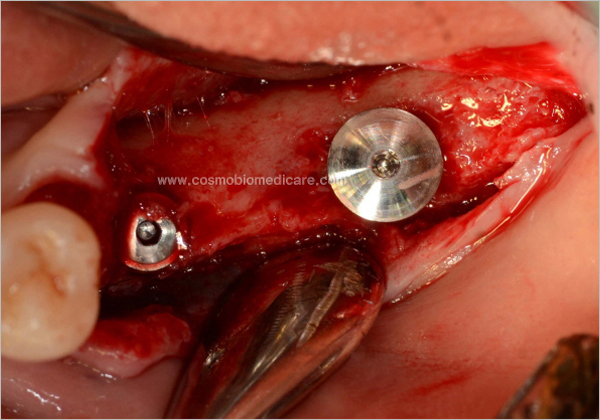

Clinical Cases

• Case1

• Case2

• Case3

• Case4

• Case5

• Case6

• Case7

• Case8

• Case9

• Case10